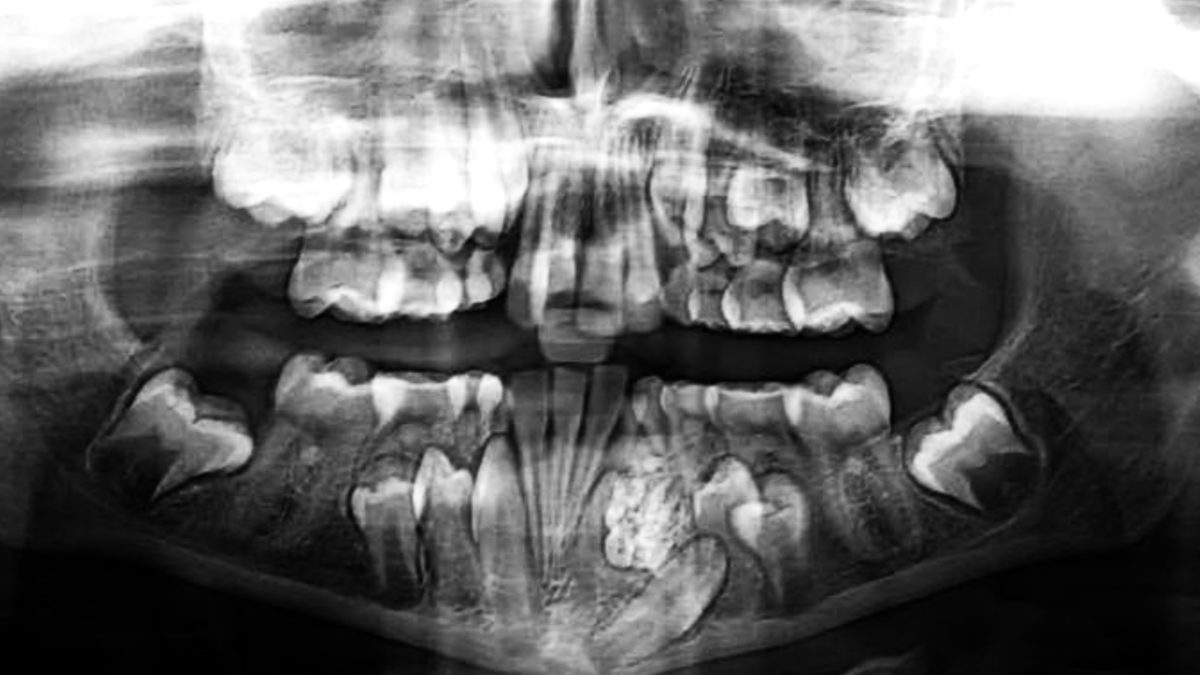

An adult human being has 32 teeth, including wisdom teeth. 16 on the upper jaw, 16 on the lower. So, how did a 17-year-old boy wind up with a colossal 232 teeth being removed from his jaw – roughly the same amount as some species of shark?

Well, don’t worry, the doctors were as confused as you are. The boy in question was Ashik Gavai, who turned up at a doctor’s office in 2014, in Mumbai, India, with a swelling in his lower jaw. The perplexed physician couldn’t figure out the cause and referred him to the city’s JJ hospital.

Dhivare-Palwankar eventually diagnosed Gavai with “complex odontoma“, a benign tumor linked to tooth development. He booked him in for surgery, but even that went far beyond what he expected. As he said:

“We operated on Monday and it took us almost seven hours. We thought it may be a simple surgery but once we opened it there were multiple pearl-like teeth inside the jaw bone.”

After painstakingly removing countless “pearl-like” teeth, the surgeons were confronted by another perplexing situation, a large “marble-like” structure that couldn’t simply be removed. And so they begin forcefully chiseling out the solid chunk, taking it out in fragments.

Dhivare-Palwankar believed at the time that 232 teeth would be a new “world record” for the number of teeth in a person. He may have been right, but in 2019, another Indian boy had a colossal 526 teeth removed from his jaw. I’m sure he was overjoyed to be the new record-holder.